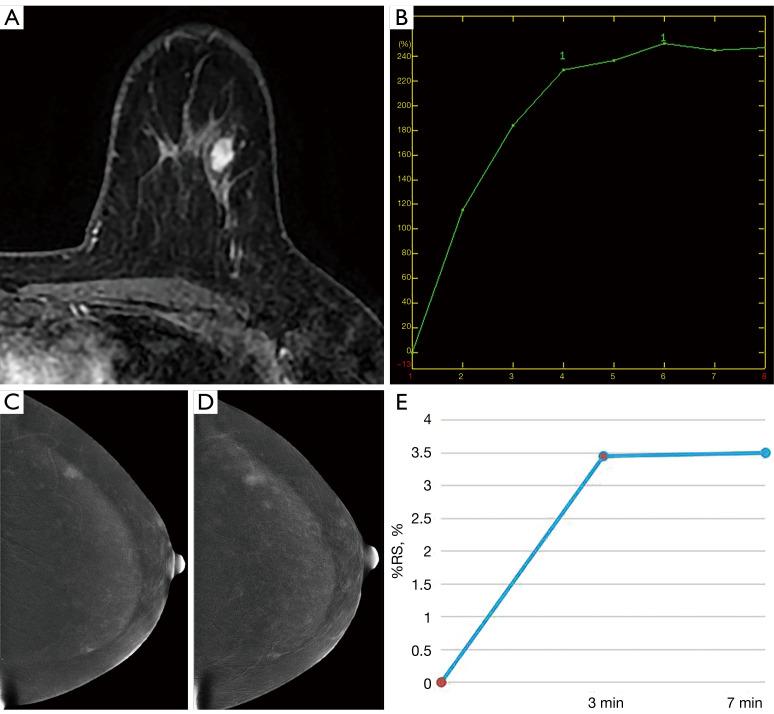

The Kaiser score (KS) as a clinical decision rule has been proven capable of enhancing the diagnostic efficiency for suspicious breast lesions and obviating unnecessary benign biopsies. However, the consistency of KS in contrast-enhanced mammography (CEM-KS) and KS on magnetic resonance imaging (MRI-KS) is still unclear. This study aimed to evaluate and compare the diagnostic efficacy and agreement of CEM-KS and MRI-KS for suspicious breast lesions.

This retrospective study included 207 patients from April 2019 to June 2022. The radiologists assigned a diagnostic category to all lesions using the Breast Imaging Reporting and Data System (BI-RADS). Subsequently, they were asked to assign a final diagnostic category for each lesion according to the KS. The diagnostic performance was evaluated by the area under the receiver operating characteristic curve (AUC). The agreement in terms of the kinetic curve and the KS categories for CEM and MRI were evaluated via the Cohen kappa coefficient.

The AUC was higher for the CEM-KS category assignment than for the CEM-BI-RADS category assignment (0.856 . 0.776; P=0.047). The AUC was higher for MRI-KS than for MRI-BI-RADS (0.841 . 0.752; P =0.015). The AUC of CEM-KS was not significantly different from that of MRI-KS (0.856 . 0.841; P=0.538). The difference between the AUCs for CEM-BI-RADS and MRI-BI-RADS was not statistically significant (0.776 . 0.752; P=0.400). The kappa agreement for the characterization of suspicious breast lesions using CEM-KS and MRI-KS was 0.885.

The KS substantially improved the diagnostic performance of suspicious breast lesions, not only in MRI but also in CEM. CEM-KS and MRI-KS showed similar diagnostic performance and almost perfect agreement for the characterization of suspicious breast lesions. Therefore, CEM holds promise as an alternative when breast MRI is not available or contraindicated.